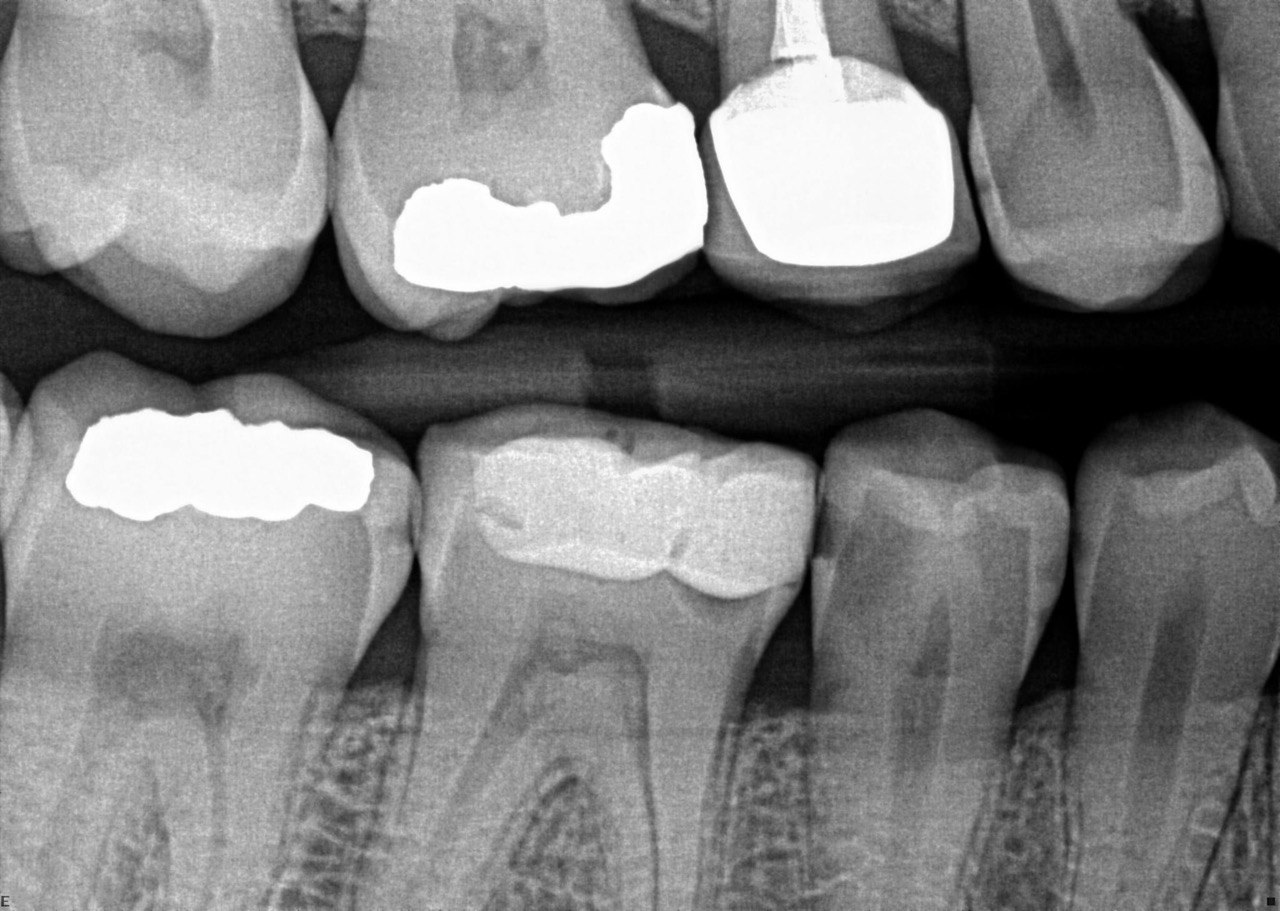

Question 2. What is the condition of the mesial of the tooth # 2.7?

Question 3. What is the condition of the distal surface of the tooth # 2.7 and mesial surface of the tooth # 2.8 respectively?